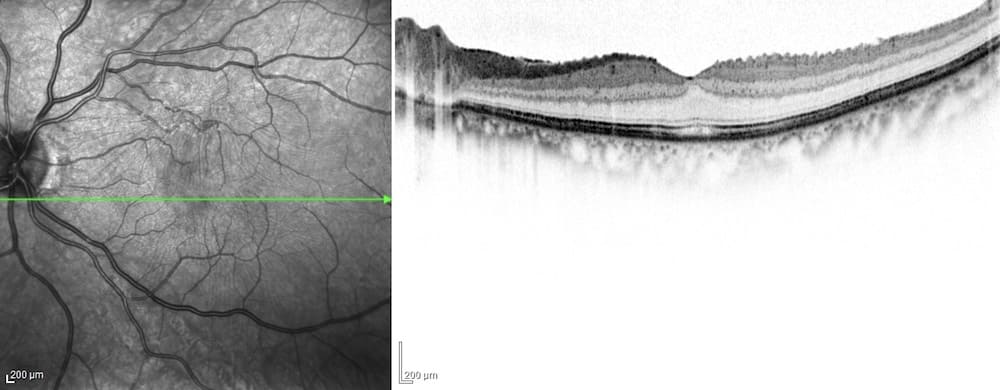

加齢などによって硝子体が縮み、硝子体が網膜から離れることによって起こる病気です。網膜の表面に残った硝子体の細胞が増殖し、セロハンのような膜(黄斑前膜)が形成されることで、物が歪んで見えたり、物が大きく見えるなどの症状が出現します。程度にもよりますが、進行してくると網膜は不可逆性の変性を生じ視力の回復が難しくなる場合があり、適切な時期での手術が望ましいと考えられます。硝子体手術では貼りついている黄斑前膜を除去し、視力の改善を図ります。